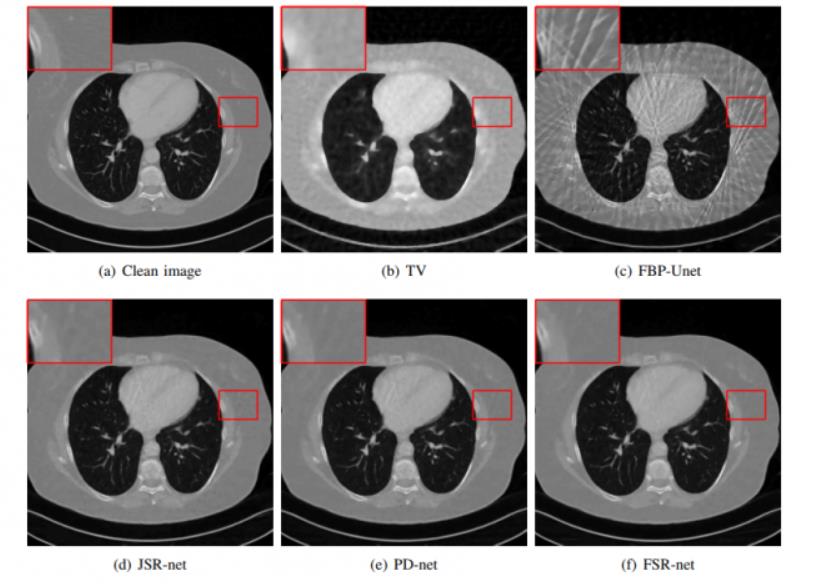

针对CT图像不完备成像问题, 课题组提出了有效的重建模型和算法, 并运用卷积神经网络建立端到端的可学习化模型。如图所示, 我们提出的方法可以有效的减少图像中的伪影现象, 相关工作发表于IEEE Transactions on Computational Imaging。